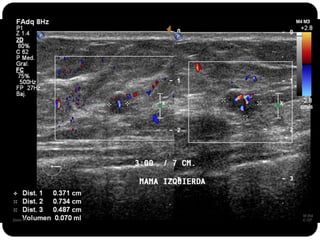

Paciente femenina de 66 años con historia clínica de 1er gesta antes de los 30 años y antecedentes de lactancia positiva, presenta una lesión palpable en la mama derecha. Los estudios radiológicos indican un diagnóstico de bi-rads 5, con biopsias revelando adenocarcinoma lobulillar infiltrante en la glándula mamaria derecha y adenocarcinoma ductal in situ en la izquierda. El caso fue evaluado por las doctoras Jacqueline Preciado Vargas y Beatriz E. González Ulloa.